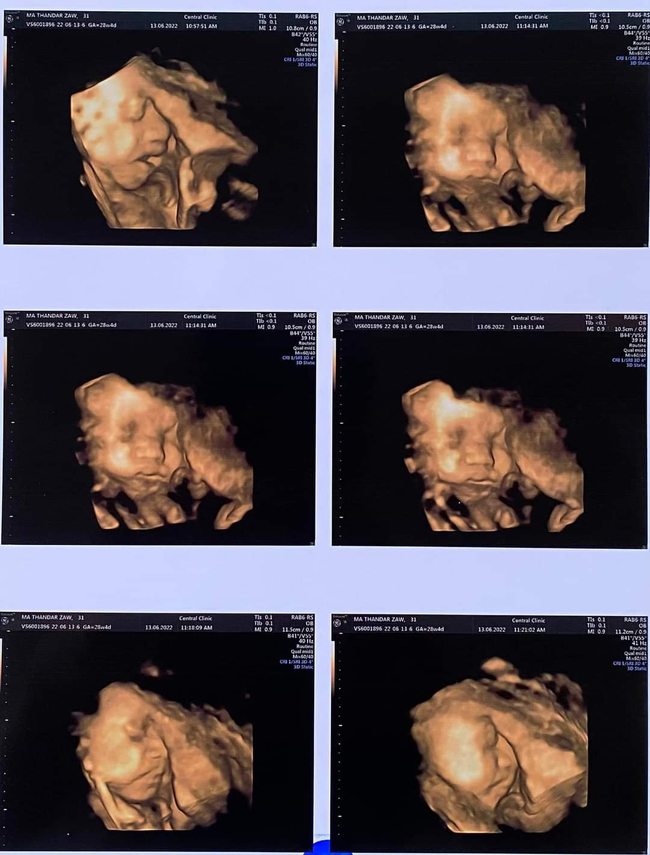

သူမရဲ့ဗိုက်ထဲက သမီးလေးကို အာထရာဆောင်းရိုက်ခဲ့ပြီး ဒီပုံလေးတွေကို Facebookပေါ်ဝေမျှခဲ့ပါတယ်။

သူမရဲ့ ဗိုက်ထဲက အခုတည်းက သူ့အဖေသားဂန်းအကျင့်စရိုက်တွေတူနေပြီဆိုတာကိုလည်း အခုလိုရေးသားခဲ့ပါသေးတယ်

"အမေရဲ့အချင်းနားကကိုမျက်နှာမခွာတာ?

သူ့မျက်နှာလေးအပြည့်ကို 4Dရိုက်မရဘူး??

သူအဖေအတိုင်းပဲကင်မရာမကြိုက်သောလေး?

အဖေနဲ့တူချင်ရင် ပါးချိုင့်လေးရယ် အသံလေးရယ်တူနော်သမီး?"